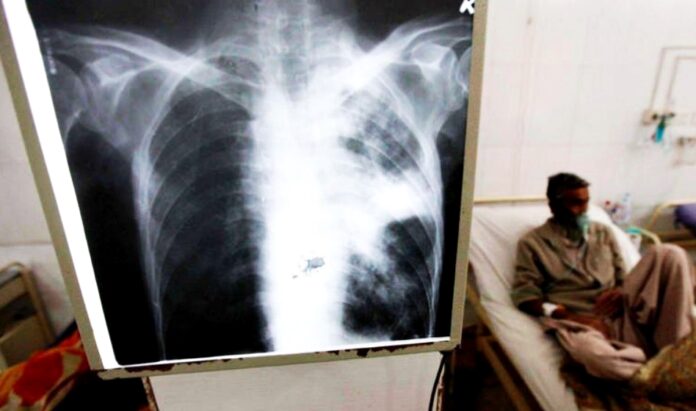

La tuberculosis, según describe el Ministerio de Salud de la Nación, es una enfermedad prevenible, tratable y curable causada por una bacteria llamada Mycobacterium tuberculosis, también conocida como bacilo de Koch. De acuerdo a la localización de la enfermedad, se habla de tuberculosis pulmonar, cuando el órgano afectado es el pulmón. Esta es la forma más común en la que se presenta.

La forma más común de contagio de la tuberculosis es a través del aire, cuando una persona con tuberculosis pulmonar activa tose, estornuda o habla, liberando bacterias al ambiente. Estas bacterias pueden ser inhaladas por otras personas y causar la infección. El contagio es más probable en espacios cerrados y/o con poca ventilación, donde las bacterias pueden permanecer en el aire durante más tiempo.